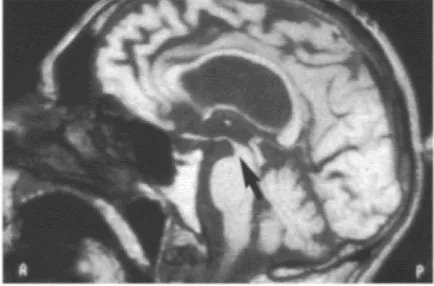

Imaging changes in PSP include both generalized and selective brain stem atrophy (Figure 29). Single photon emission computed tomography (SPECT) can demonstrate impairment of frontal perfusion with an intact cortical rim. PET scanning shows decreased metabolic activity in the frontal cortex, caudate and putamen, together with evidence of abnormal D2 receptor function (Figure 30).

Figure 29 Progressive supranuclear palsy: sagittal T1-weighted MRI showing midbrain atrophy. Courtesy of M.Savoiardo, Department of Neuroradiology, Istituto Nazionale Neurologico âC.Bestaâ, Milan, Italy